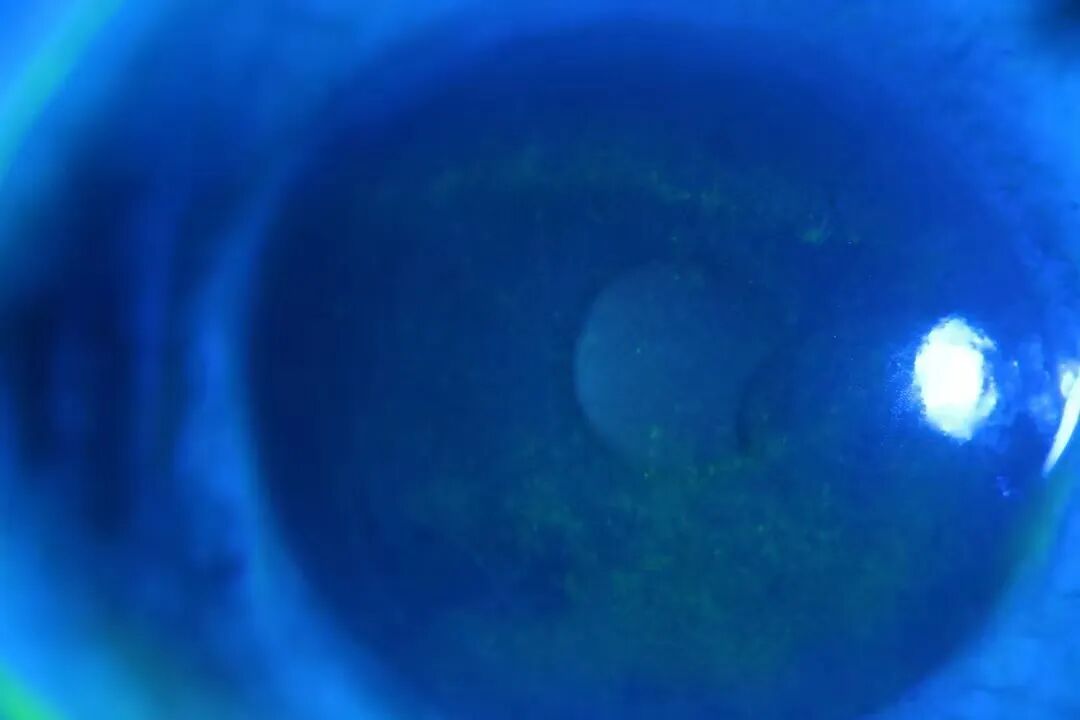

▲来医院就诊时的眼睛外观图(左滑查看)

“直到发现眼睛怎么一坨白白的才过来看。”

接诊医生廉庆博士表示,小文这种情况是眼球挫伤,受伤后没有第一时间前来处理,拖了三天导致病情恶化,对视力造成了很大的影响。